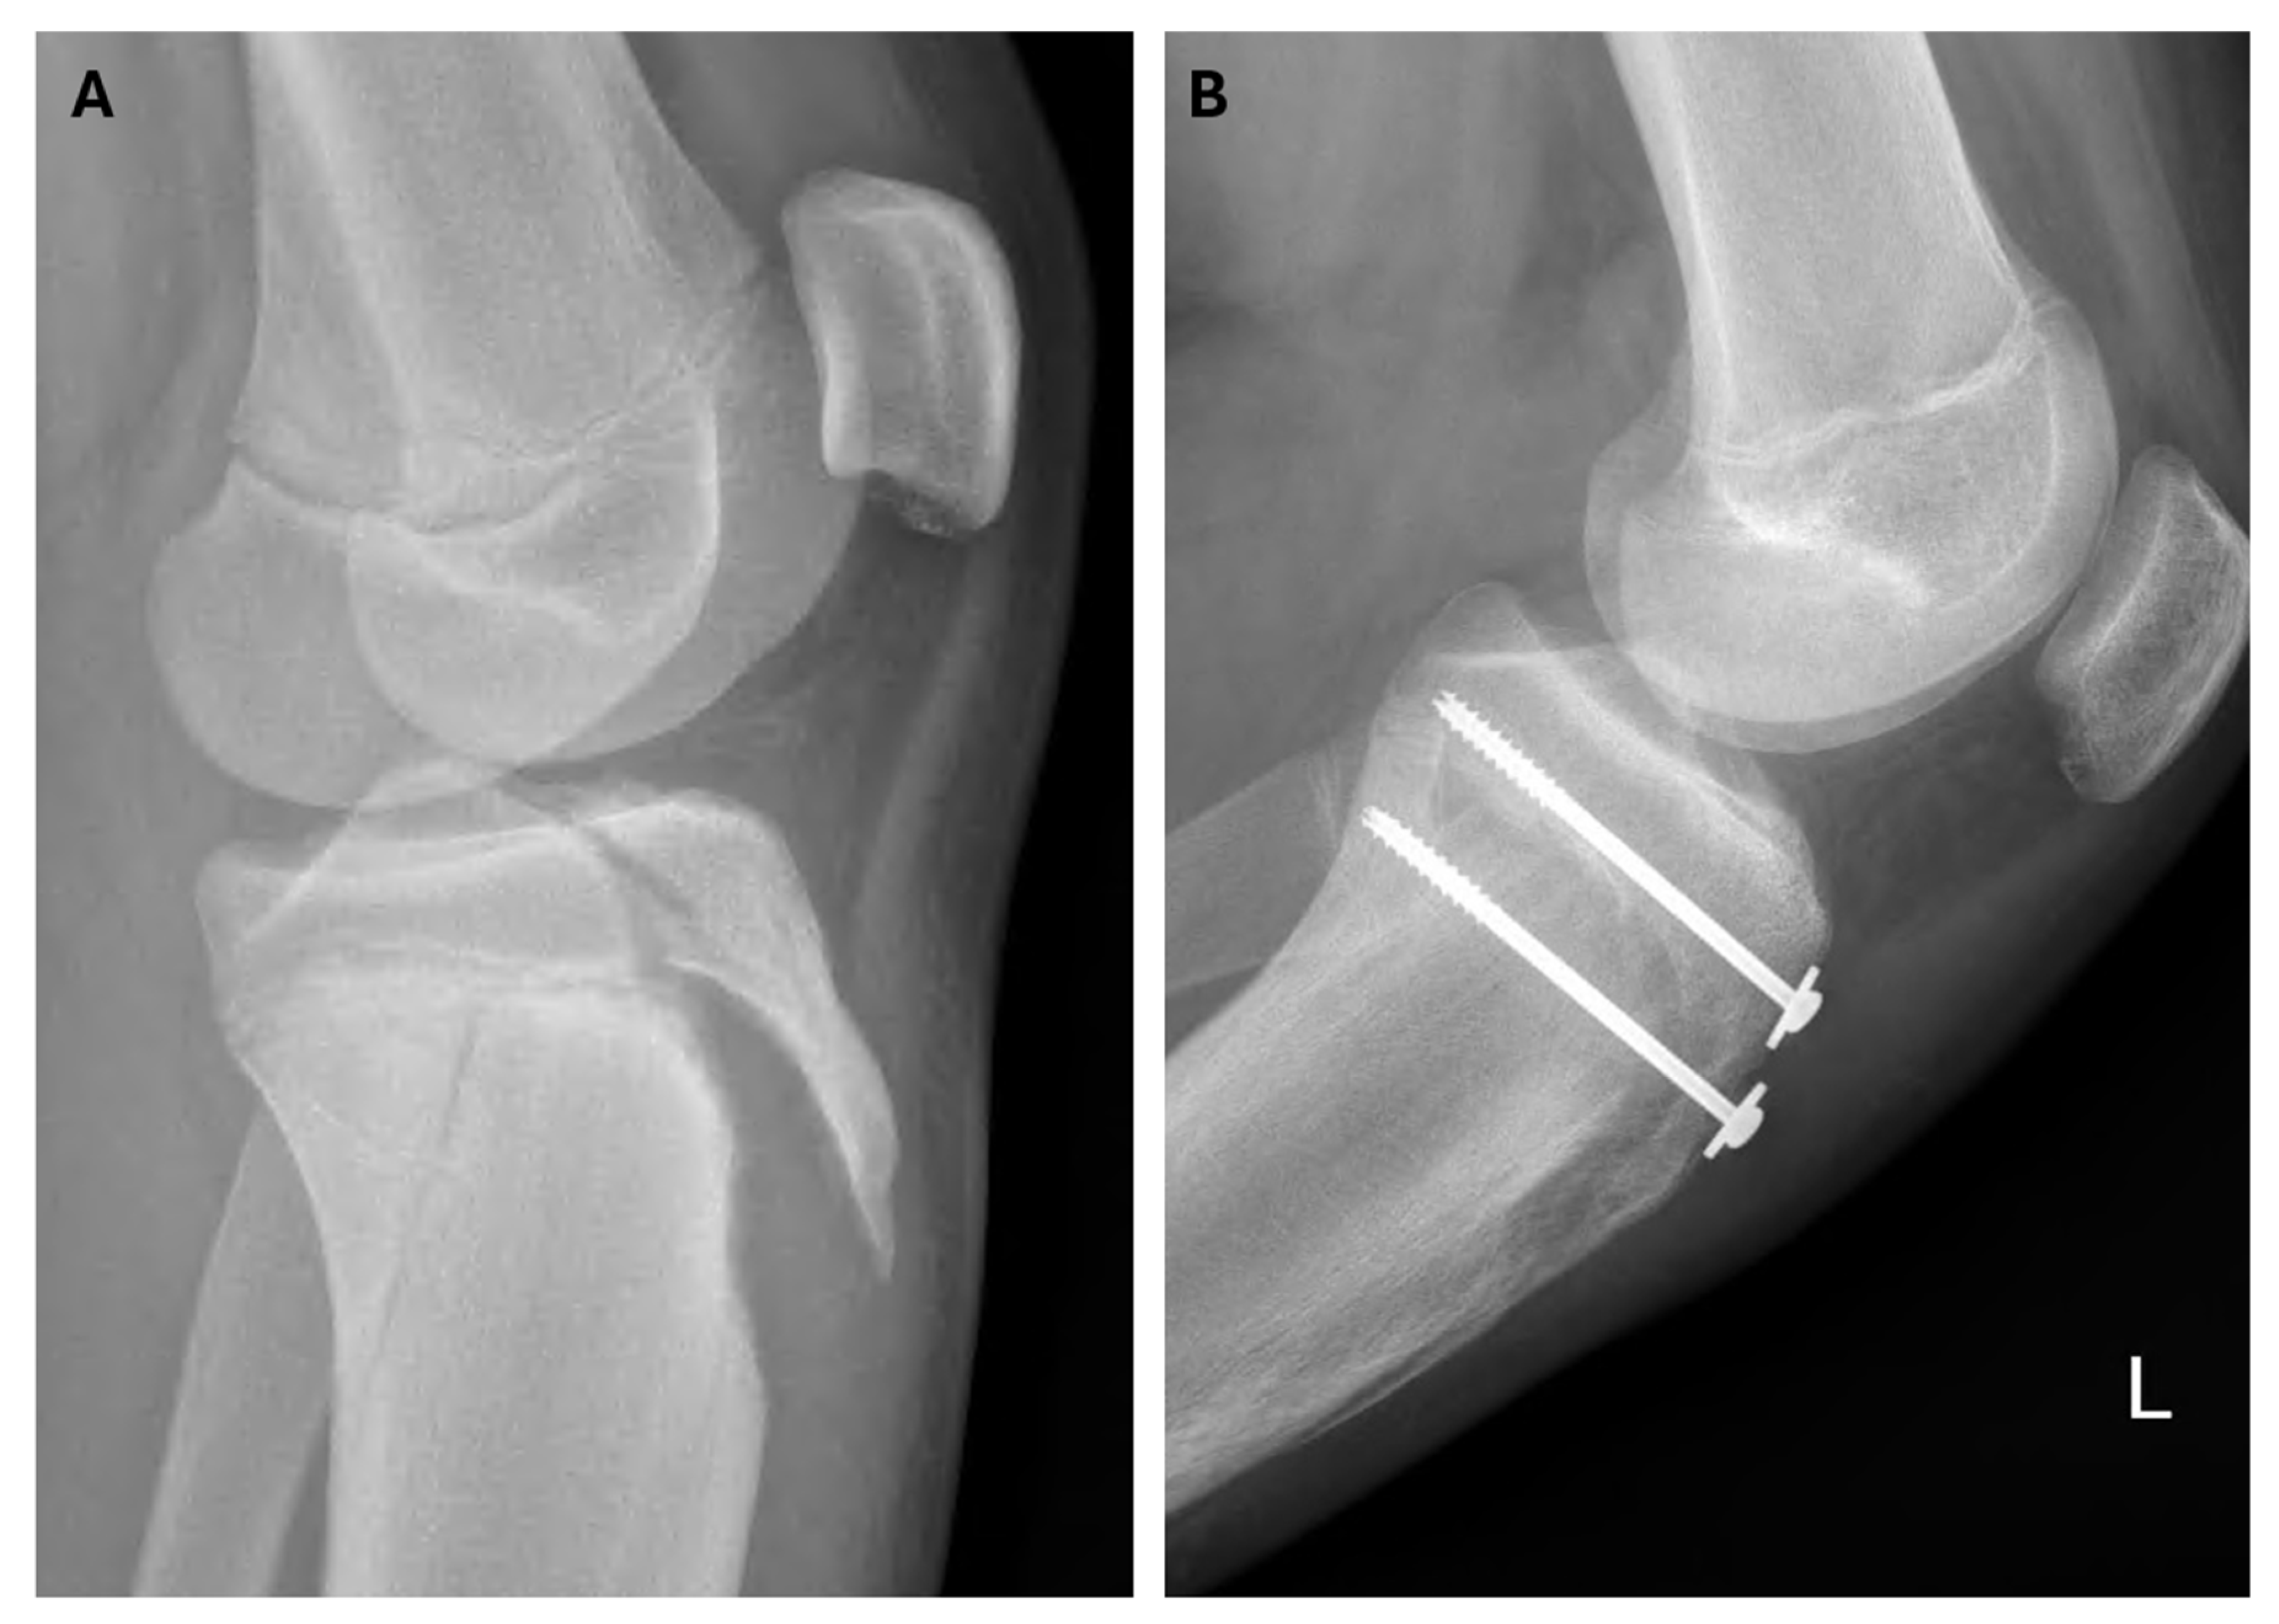

| 4 | Soccer | - | IIIb | ORIF | screws | - | - | 11.6 |

| 10 | Soccer | - | IIIb | ORIF | screws | patellar ligament | - | 9.2 |

| 14 | Soccer | CT | IIIa | ORIF | screws | quadriceps tendon | - | 7.4 |

| 18 | Soccer | CT | IIIa | ORIF | screws | patellar ligament | - | 9.7 |